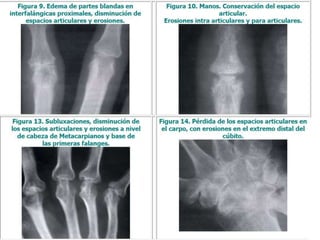

HALLAZGOS RADIOGRÁFICOS

RADIOGRAFÍAS

•Manos

•Pies

•Tórax

Evaluación

inicial:

• Inicialmente sin hallazgos tempranos

• 2 años de la enfermedad sin control:

– Erosión ósea y destrucción del cartílago

• Osteopenia periarticular

• Disminución del espacio articular por pérdida

de cartílago con erosión yuxtaarticular

• Finalmente erosiones quísticas óseas